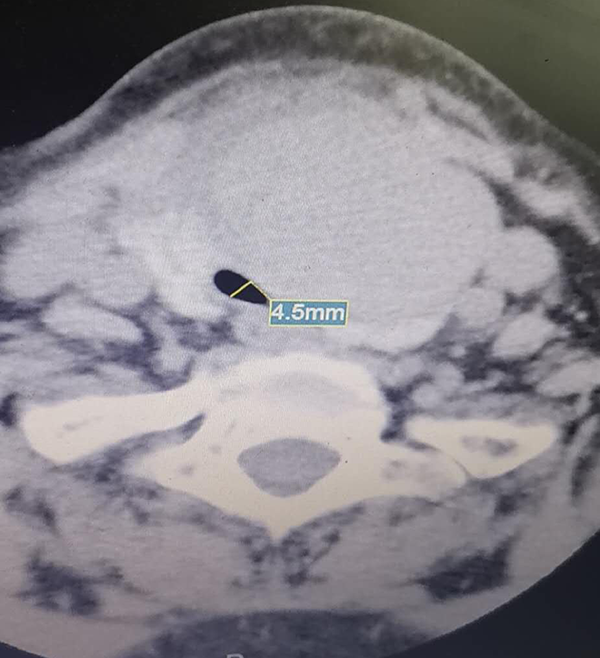

患者必须立即手术,解除气管压迫,否则随时可能窒息死亡,但患者的气管已经严重受压偏移,最狭窄处仅有4.5毫米,时间就是生命,一刻也不能耽误,朱珲医师立即汇报吴卫高副院长,提前与相关科室急会诊讨论,尽快拟定手术方案。围绕患者的危急病情,麻醉科魏俊生主任、吴凤琴主任、普外科叶临生主任、徐坤医师、耳鼻喉科杨峰主任、超声科吴才田主任都第一时间赶到病房讨论病情,而且远在合肥的安徽省肿瘤医院王圣应主任也给予指导,大家一致意见虽然手术风险极大,但预先在超声引导下减压再清醒气管插管急诊手术可以使成功率能大大提高。

患者术前颈部CT